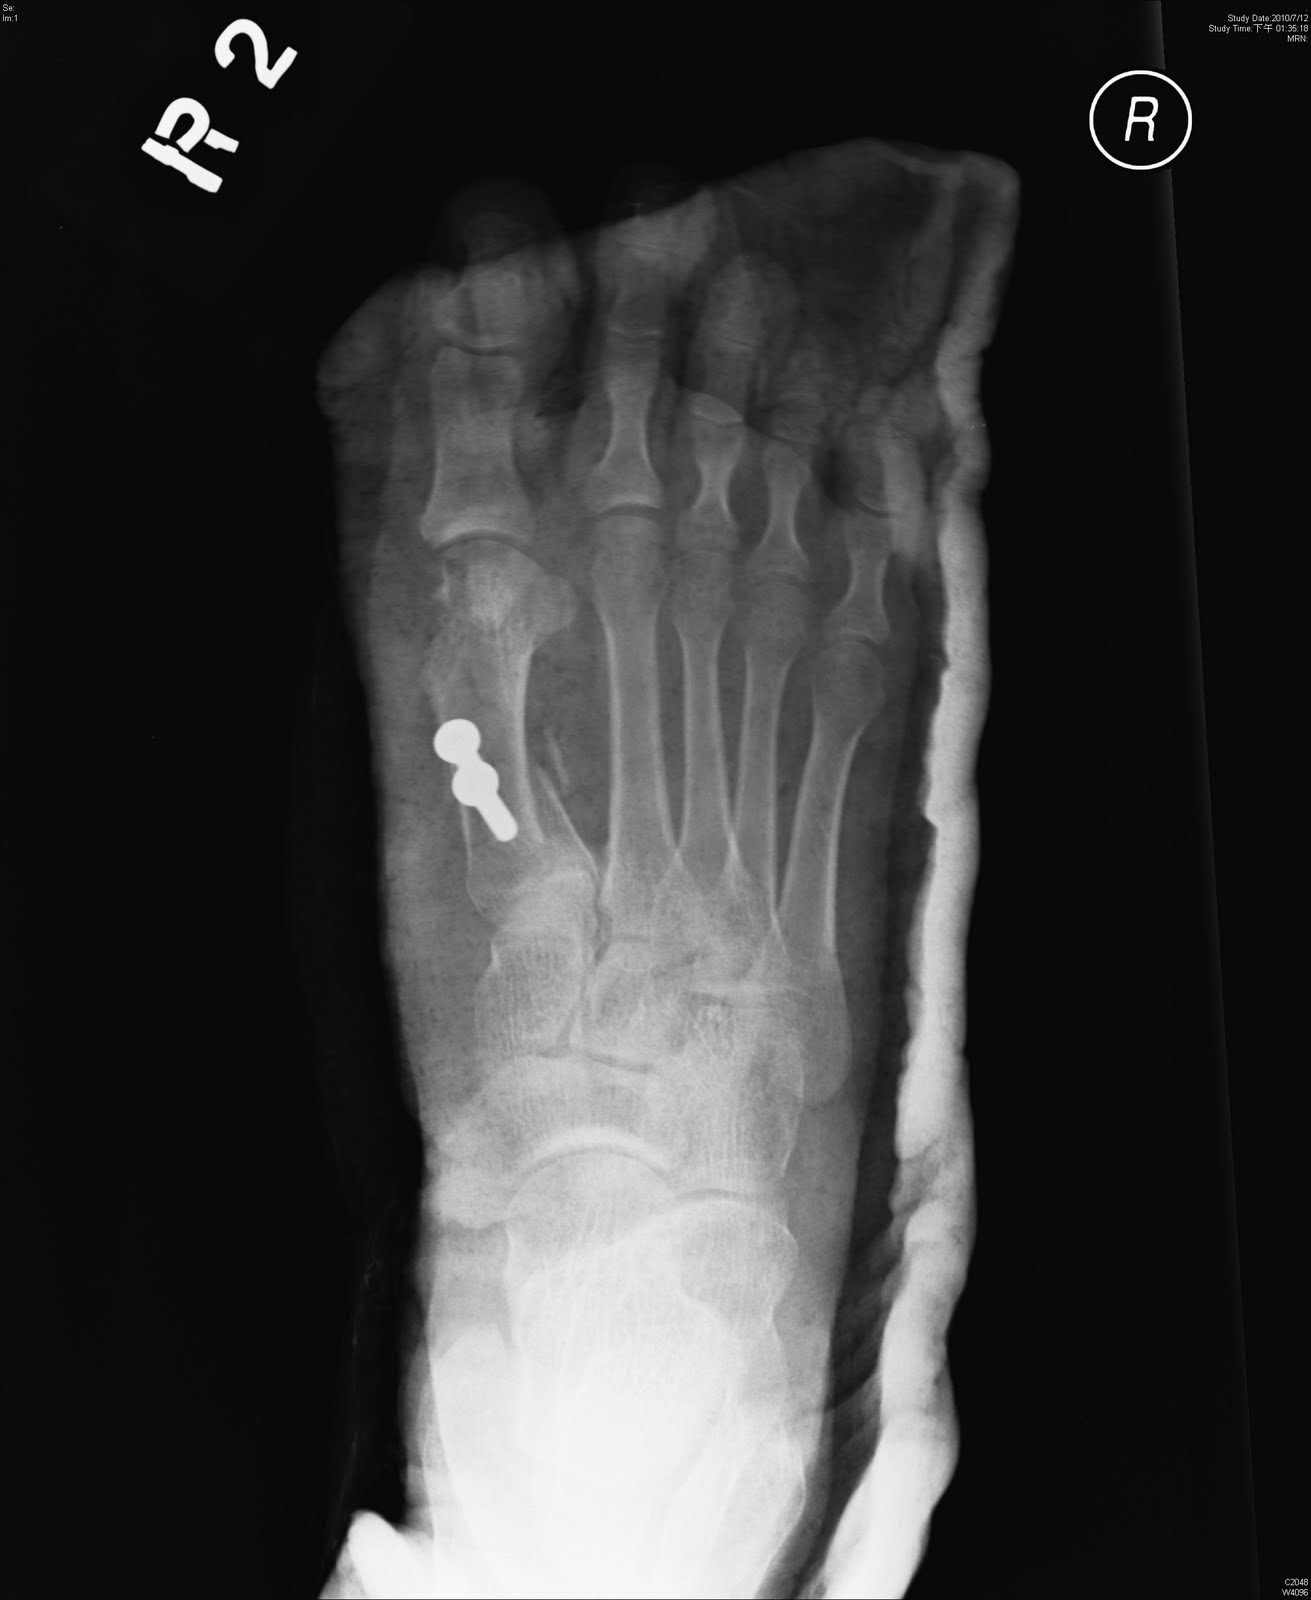

He or she will check for. For decades healthcare organizations have asked for more detail regarding fractures. Learn vocabulary, terms and more with flashcards, games and other study tools. Unsp fracture of right foot, init encntr for closed fracture. You can always come back for icd 10 code for right foot fracture because we update all the latest coupons and special deals weekly. • the original injury code will follow the patient. Any cut, fracture, burn or scrape gives bacteria an entry point. Displaced fracture of third metatarsal bone, right foot. Unspecified fracture of right foot, initial encounter for closed fracture. Coders will need very specific information in order to code for fractures. Insect bite or sting, venomous (t63.4). Generally speaking, every character to the right of the decimal point adds its own element of meaning. Most of the codes in chapter 13 contain site and laterality designations. Conditions that weaken your immune system such as diabetes. Applicable from 10/01/2019 through 09/30/2020. Show additional info hide additional info. How is a foot fracture diagnosed?